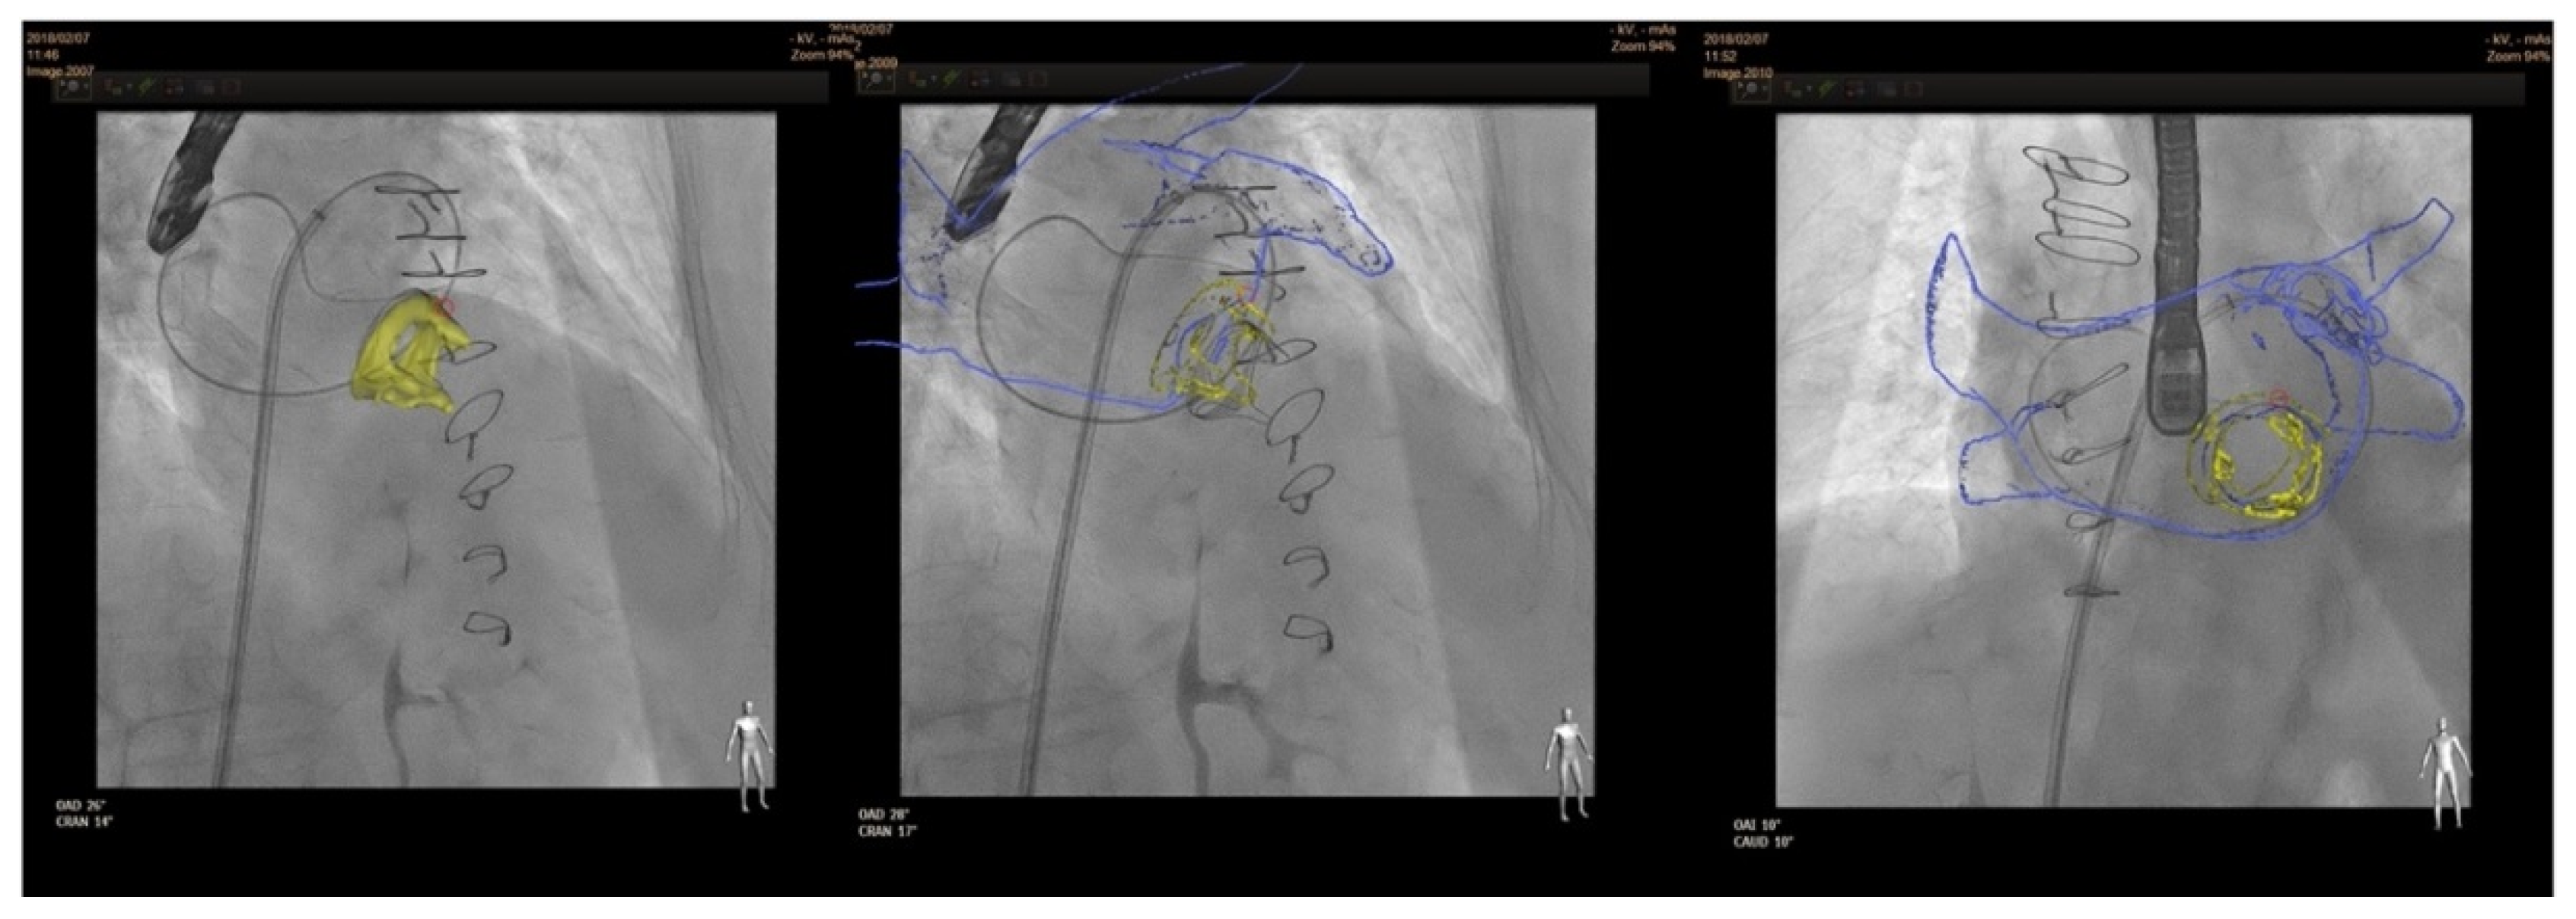

4.3. Procedure

4.3.1. Anterograde Approach